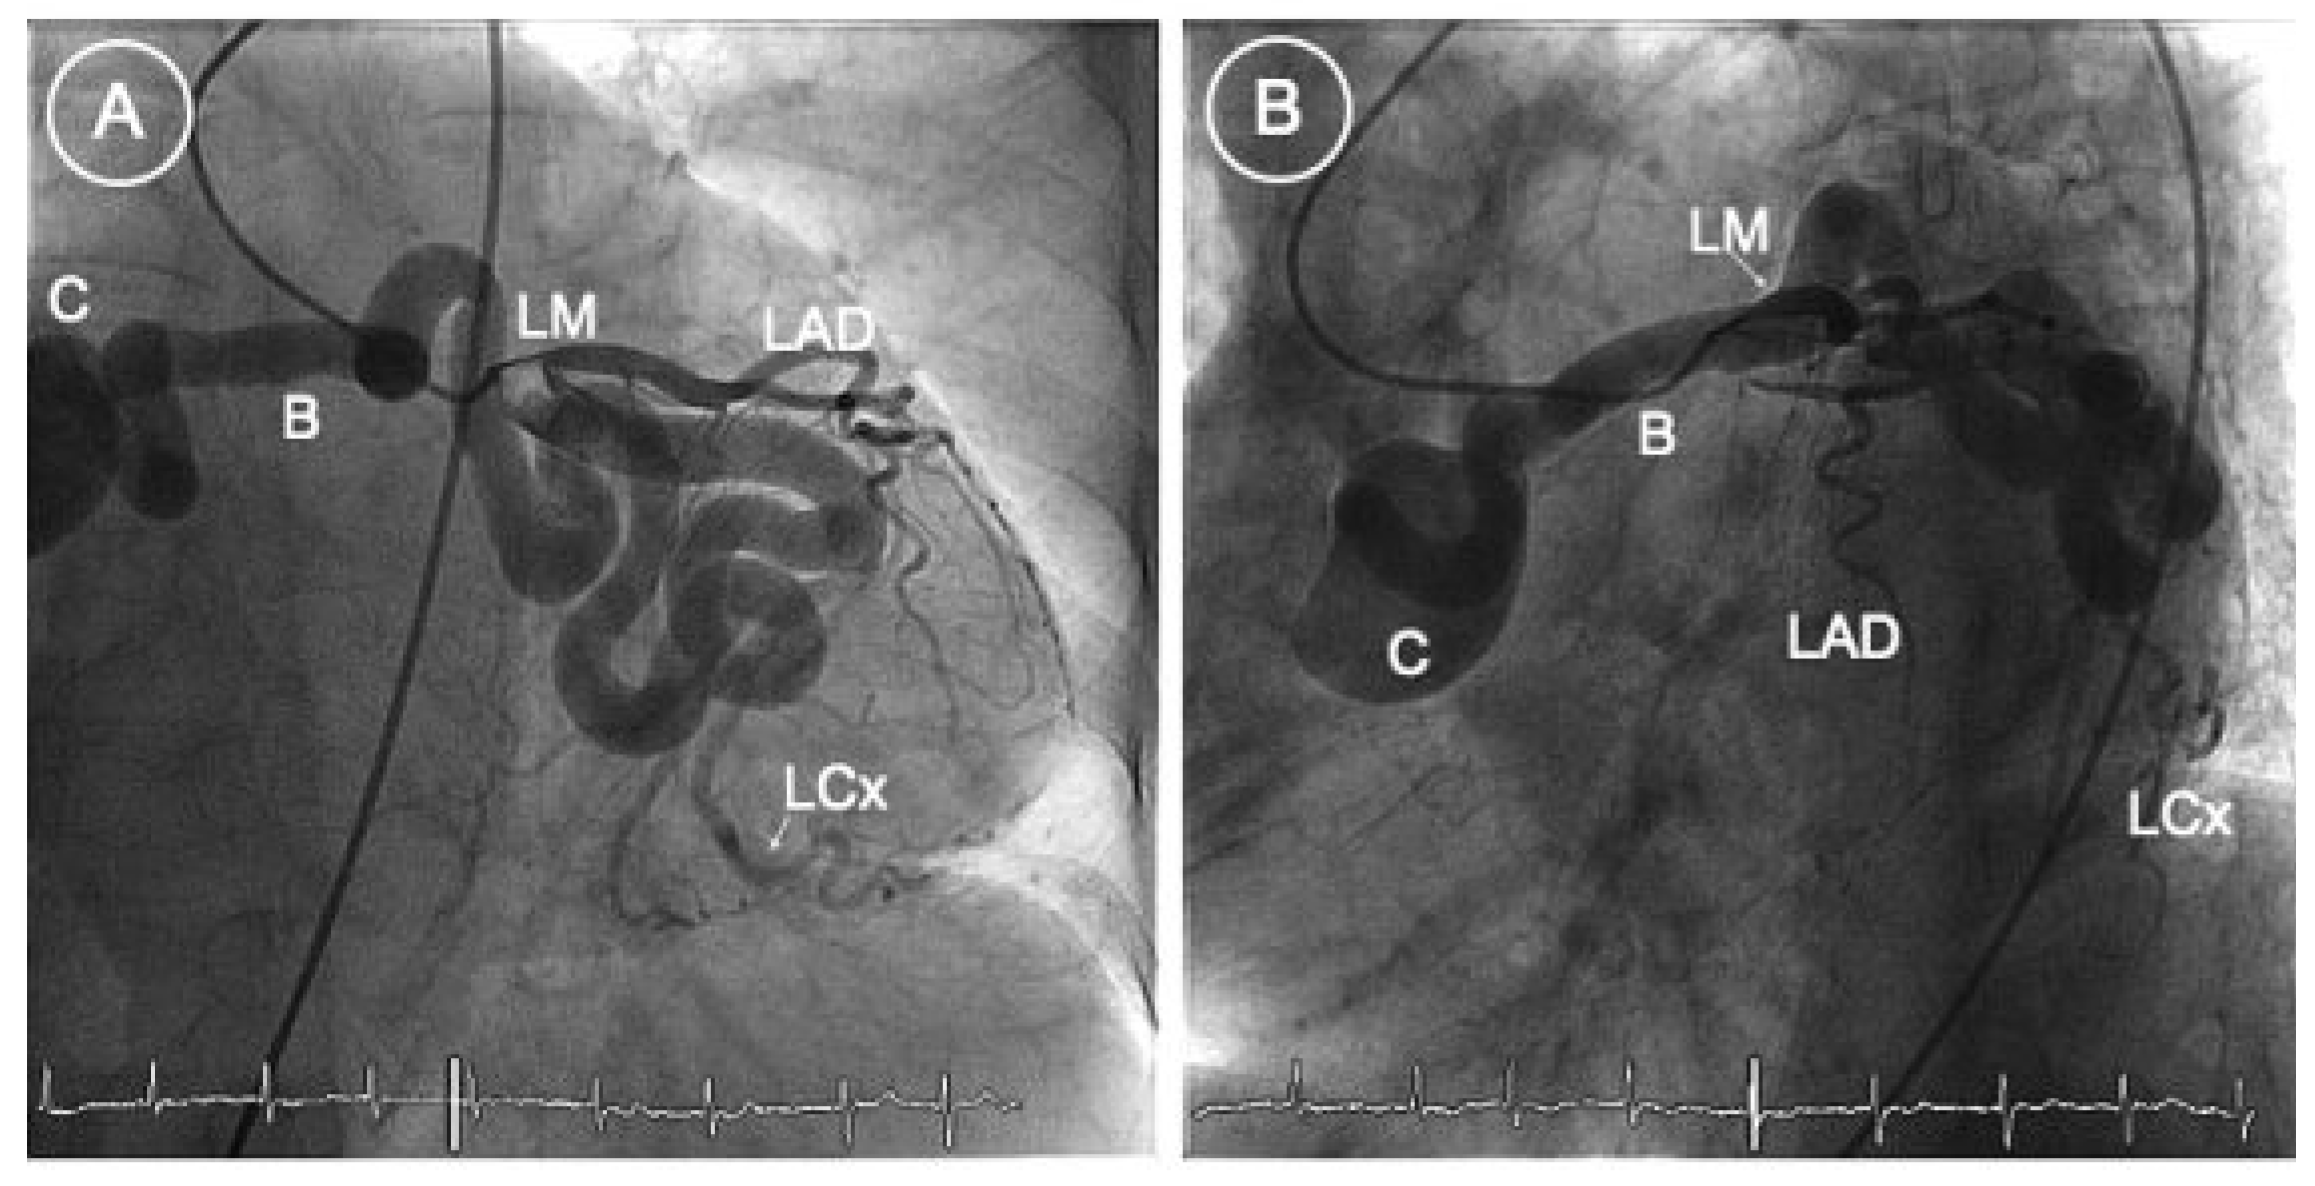

Figure 1.

RAO (A) and anteroposterior (B) caudal views. LM = left main coronary artery; LAD = left anterior descending artery; LCx = left circumflex artery; B = body of the giant fistula; C = collet of aneurysmal formation before reaching the right atrium.